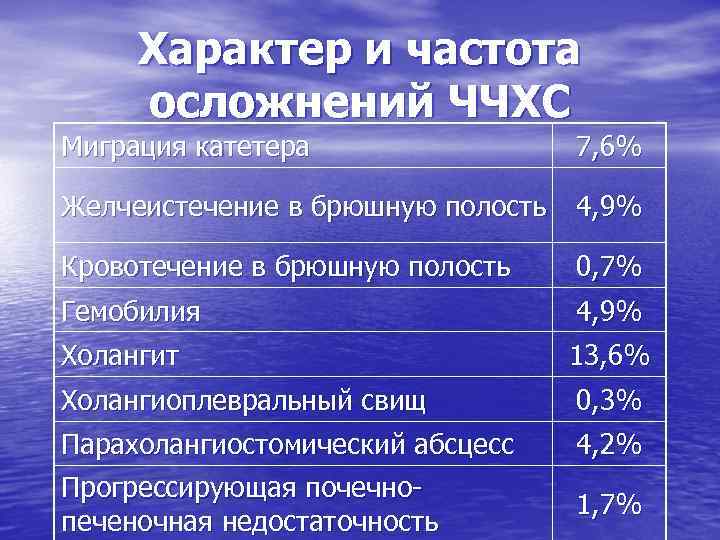

Характер и частота осложнений ЧЧХС Миграция катетера 7, 6% Желчеистечение в брюшную полость 4, 9% Кровотечение в брюшную полость 0, 7% Гемобилия 4, 9% Холангит 13, 6% Холангиоплевральный свищ 0, 3% Парахолангиостомический абсцесс 4, 2% Прогрессирующая почечнопеченочная недостаточность 1, 7%